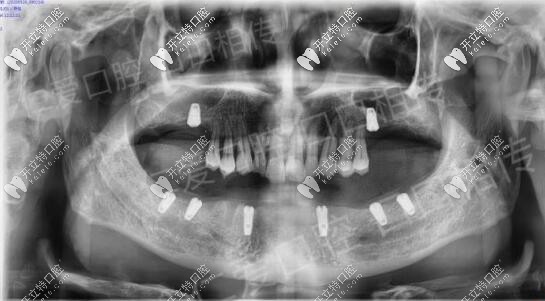

年前來到醫(yī)院口腔咨詢種植牙,上頜先種2顆,下頜把松牙拔除,等待恢復后下頜做all-on-6,種6顆,恢復半口。

疫情前把該拔的殘根松動牙拔除恢復到現在,主要設計的ALL-ON-N種6恢復下半口,今天已成功種植8顆植體

術后裝上過渡性樹脂義齒,等待種植體與骨質結合較好之時再進行長久性牙齒佩戴,老爸現在咀嚼穩(wěn)定健康,重啟生活質量,他高興,我也感覺欣慰。